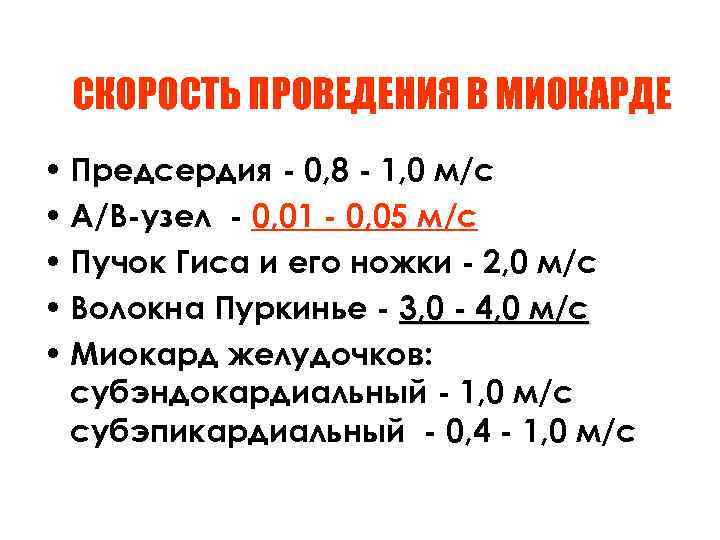

СКОРОСТЬ ПРОВЕДЕНИЯ В МИОКАРДЕ • Предсердия - 0, 8 - 1, 0 м/с • А/В-узел - 0, 01 - 0, 05 м/с • Пучок Гиса и его ножки - 2, 0 м/с • Волокна Пуркинье - 3, 0 - 4, 0 м/с • Миокард желудочков: субэндокардиальный - 1, 0 м/с субэпикардиальный - 0, 4 - 1, 0 м/с

СКОРОСТЬ ПРОВЕДЕНИЯ В МИОКАРДЕ • Предсердия - 0, 8 - 1, 0 м/с • А/В-узел - 0, 01 - 0, 05 м/с • Пучок Гиса и его ножки - 2, 0 м/с • Волокна Пуркинье - 3, 0 - 4, 0 м/с • Миокард желудочков: субэндокардиальный - 1, 0 м/с субэпикардиальный - 0, 4 - 1, 0 м/с

ОСОБЕННОСТИ АТРИОВЕНТРИКУЛЯРНОГО УЗЛА • Малый диаметр волокон • Множество мелких разветвлений • Низкая скорость проведения • Длительная меняющаяся рефрактерность • Блокирование быстрых повторных импульсов ( проведение с декрементом)

ОСОБЕННОСТИ АТРИОВЕНТРИКУЛЯРНОГО УЗЛА • Малый диаметр волокон • Множество мелких разветвлений • Низкая скорость проведения • Длительная меняющаяся рефрактерность • Блокирование быстрых повторных импульсов ( проведение с декрементом)